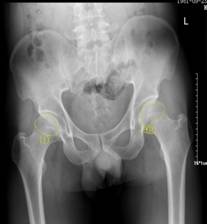

37岁的患者吴先生反复双髋疼痛2月余,听说泸州市中医院在治疗骨科疾病方面很有经验,遂来到医院治疗。经检查,吴先生双侧股骨头坏死(II期),如不及时进行手术治疗,他的股骨头将进一步坏死至骨头塌陷,引发关节炎,严重时,必须行关节置换术。这样,将会给吴先生的生活质量及经济带来严重负担。

术前报告显示患者双侧股骨头坏死